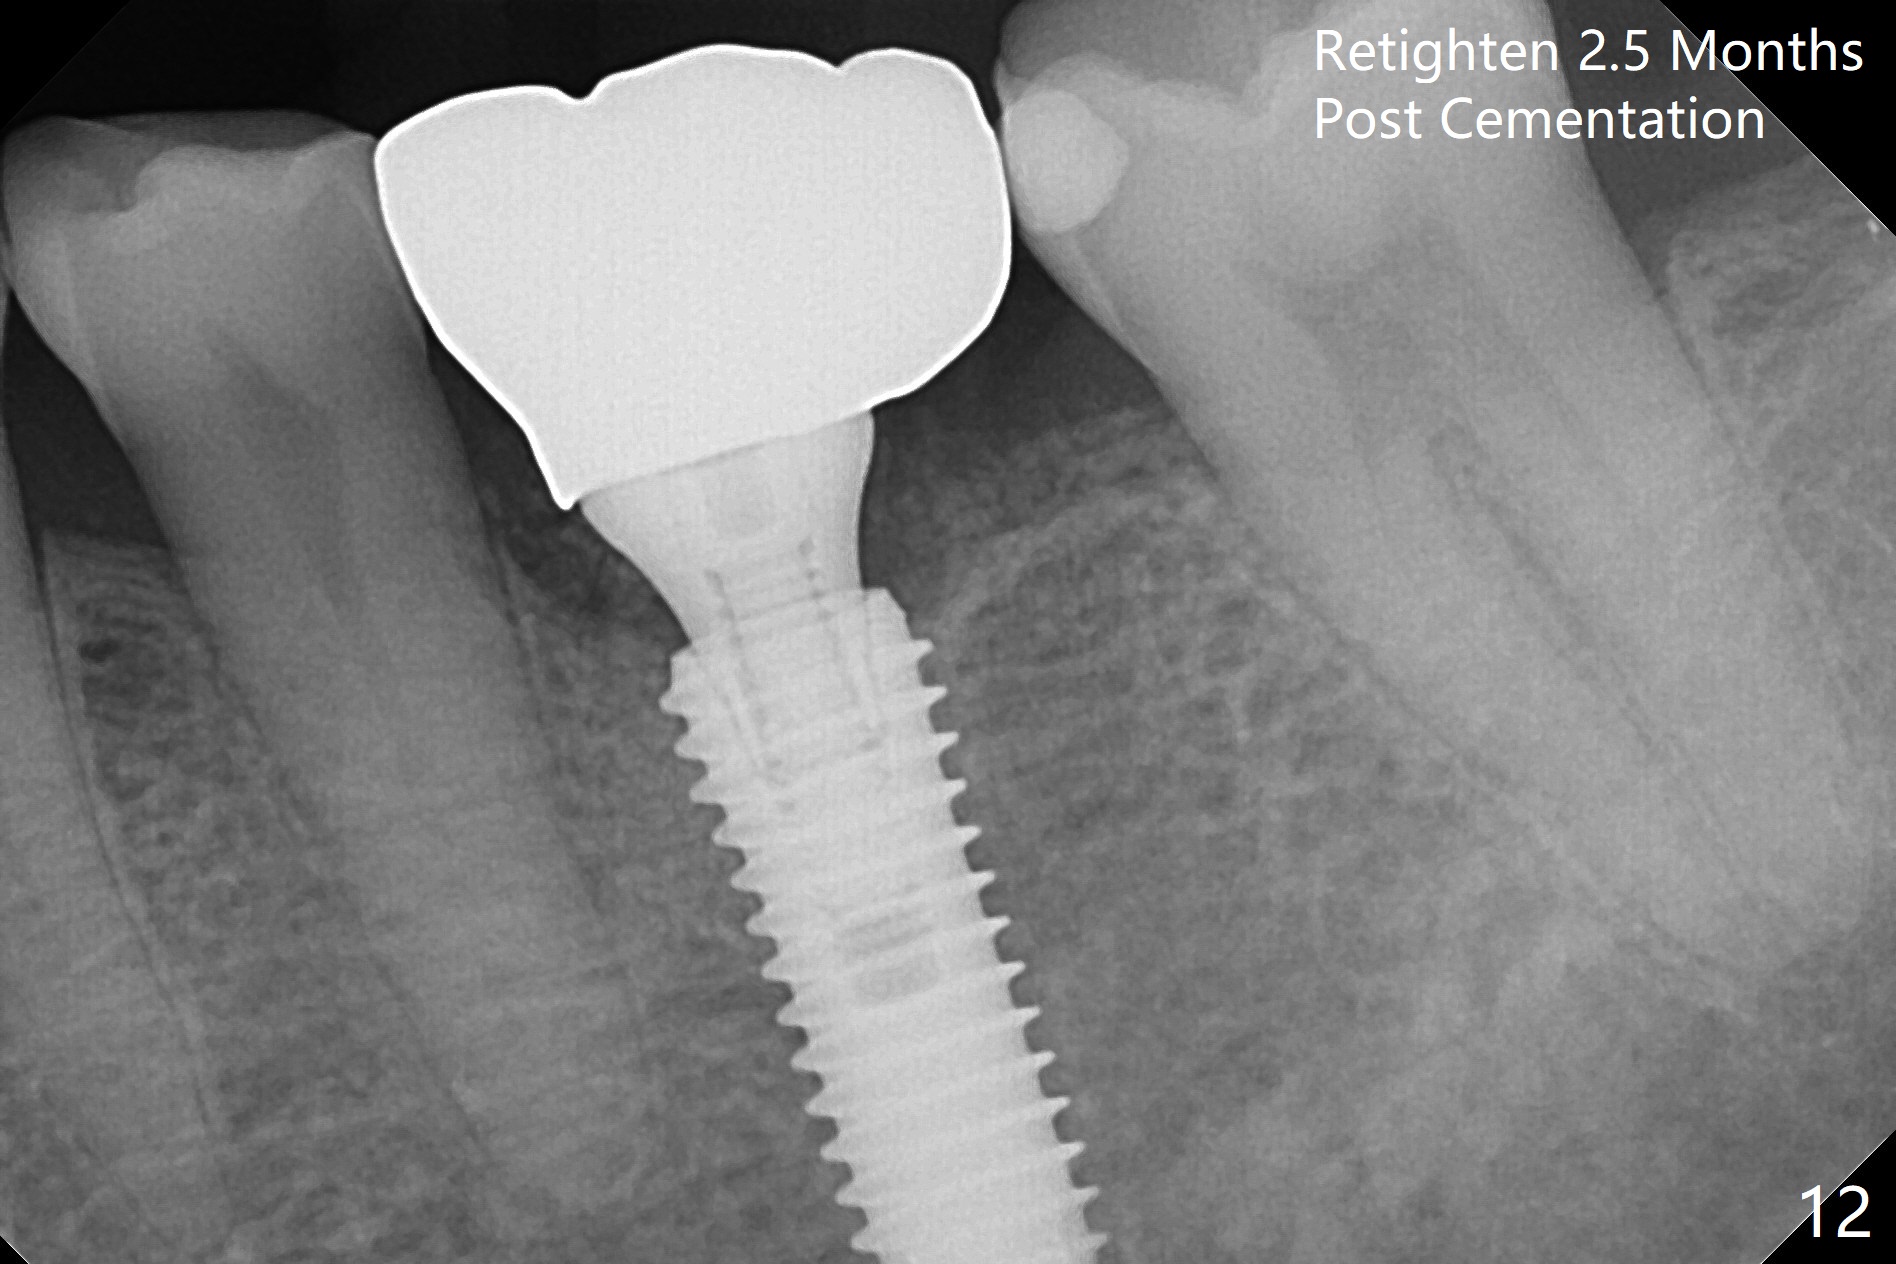

When the patient returns 9 months later, there is severe buccal gingival recession and abscess at #19 (Fig.1 *) with large mesial periradicular radiolucency (Fig.2 *).  The septum is thin and the buccal crest is low after extraction (Fig.3 * (mesial root vertical fracture)).  Osteotomy is initiated in the mesial socket immediately against the septum (Fig.4.5) with ~ 5 mm in the native bone.  Due to severe buccal plate resorption, a shorter implant is placed (Fig.6; 5x15 mm in stead of 18 mm).  There is at least 2 mm gap buccally for Vanilla Graft, which is also placed next to the implant and the neighboring root (Fig.7 *).  There is clearance from the Inferior Alveolar Canal (Fig.8 red dashed line).  Both the mesial and distal sockets heal 5.5 months postop (Fig.9), although the apical portion of the distal socket was not filled with allograft (Fig.7).  The implant was placed mesial.  The straight abutment (6.5x4(4) mm) (Fig.10) is changed to an angled one (5.5 x15 degrees 3 mm cuff (Fig.11)) before impression.  The implant is also placed buccally.  Therefore the implant position is far more important than its length.  The abutment is retightened 2.5 months post cementation, which is related to mesiobuccal placement of the implant (Fig.12).  An ideal trajectory is determined by drawing 2 horizontal lines (at crestal and apical levels: red lines in Fig.13), finding a central point of each line (vertical short line) and joining these 2 central points (Fig.14 pink line).  In fact the ideal osteotomy should have been established distal to the septum in this case.  Guided surgery may alleviate the issue.  The crown is not loose, but the patient feels that the implant tooth cannot sustain mastication.  In fact the screw is removed with hand driver (not wrench).  The abutment hex is rounded and worn.  A new 5.5x4(4) mm abutment is placed (without knowledge of previous use of an angled abutment) with mesial reduction to reduce undercut and buccodistal margin lowered to reduce gingival embrasure. It is that the straight abutment could decrease the chance of screw loosening.  Otherwise the implant has to be removed for better trajectory.